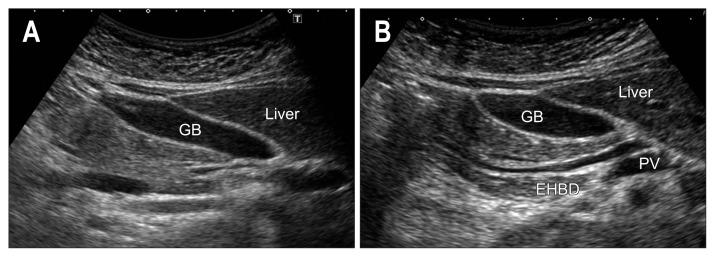

As ultrasound (US) is simple and less invasive than other imaging modalities, this technique is widely used for mass screening. However, visualizing the entire pancreas due to complicated anatomy, obesity and overlying gas can be difficult. US plays a key role in the diagnosis of pancreatic carcinoma (PC), of which tumors smaller than 10 mm (TS1a) and pancreatic carcinoma are expected to have good prognosis. To detect these forms of PC, main pancreatic duct (MPD) dilatation (3 mm or more) and pancreatic cysts (5 mm or larger) are US findings of high-risk individuals (HRIs), and these subjects should be observed periodically. Scanning maneuvers are also important for both screening for PC and follow-up of HRIs. As lesions in the groove area and ventral pancreas do not affect the MPD or extrahepatic bile duct, we should pay attention to these areas. Visualization of the tail is also challenging due to gas and stool in the alimentary tract. As the position of the pancreas changes depending on the body posture, and several different body positions should be employed, such as the right lateral decubitus, sitting, and upright positions, rather than only applying strong compression with the transducer. In cases with poor visualization, the liquid-filled stomach method is highly recommended.

由于超声(US)比其他成像方式简单且侵入性更小,因此该技术被广泛用于大规模筛查。然而,由于胰腺的复杂解剖结构、肥胖和上方气体的影响,很难对整个胰腺进行可视化。US 在胰腺癌(PC)的诊断中起着关键作用,其中直径小于 10mm(TS1a)和胰腺神经内分泌肿瘤的肿瘤预计具有良好的预后。为了检测这些形式的 PC,主胰管(MPD)扩张(3mm 或更大)和胰腺囊肿(5mm 或更大)是高危人群(HRIs)的 US 发现,这些患者应定期观察。扫描手法对于 PC 的筛查和 HRIs 的随访也很重要。由于沟区和胰头区域的病变不会影响胰管或肝外胆管,因此我们应该注意这些区域。由于消化道中的气体和粪便,尾部的可视化也具有挑战性。由于胰腺的位置随体位变化而变化,因此应采用几种不同的体位,如右侧卧位、坐位和立位,而不是仅用探头进行强力压迫。在可视化效果不佳的情况下,强烈推荐使用充满液体的胃法。